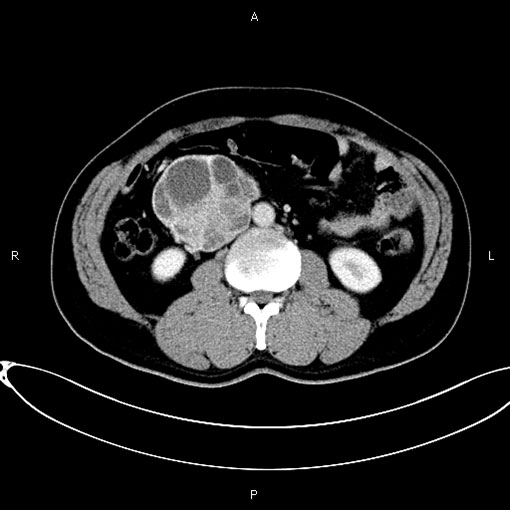

患者张某,男,44岁,主因“发现腹膜后肿物两周”入院。CT显示:右侧腹膜后团块灶囊性部分未见强化,实性部分及囊壁、分隔可见明显强化。最大截面约20×15cm,形态欠规则,边界清晰,其内见分隔影,邻近下腔静脉受压显示不清。